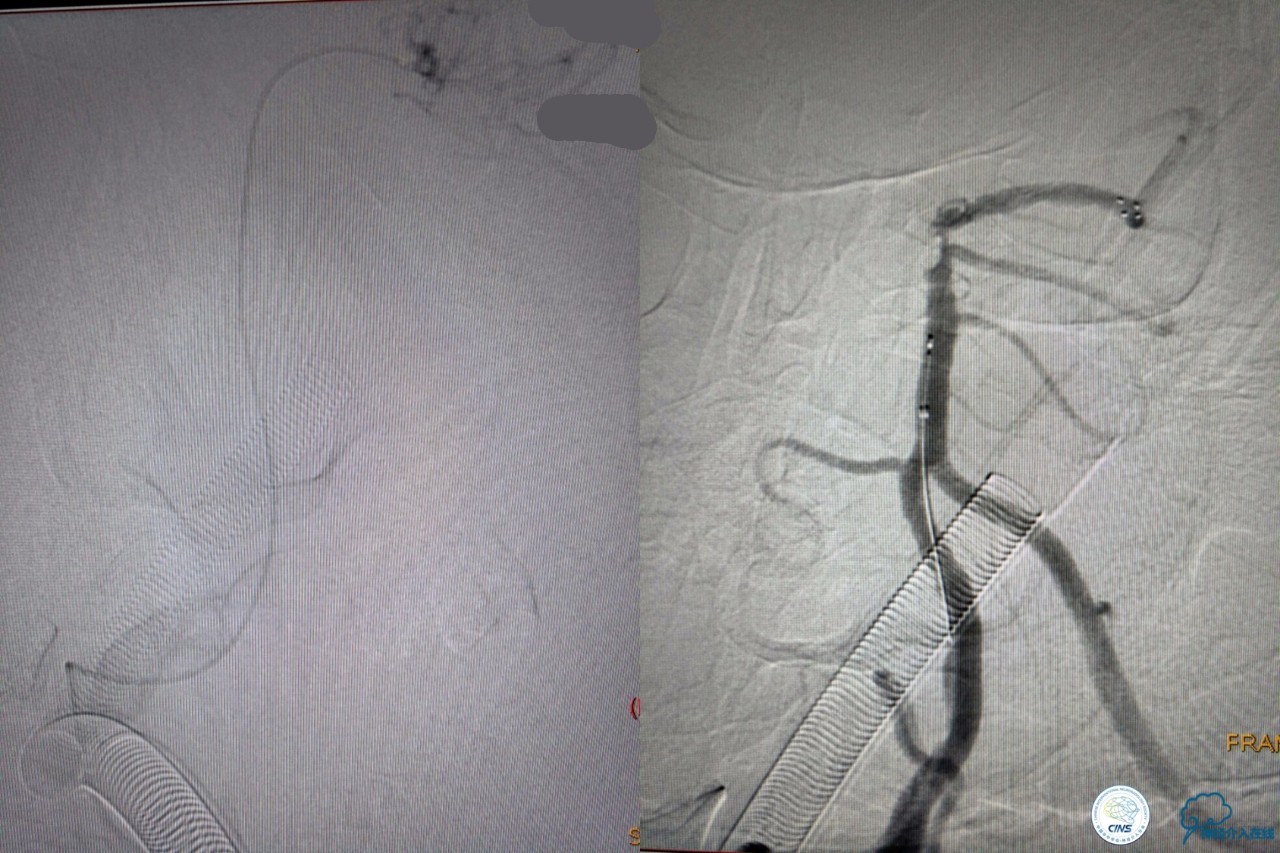

基底动脉顶端仍有大量血栓,双侧大脑后动脉未见显影,双侧小脑上动脉再通。再次取栓?还是动脉溶栓?

决定导管内给予替罗非班6ml,复查造影BA顶端仍闭塞,第二次取栓。

第二次取栓后可见基底动脉顶端仍有大量血栓,右侧大脑后动脉开通,但左侧大脑后未见显影且左侧小脑上动脉闭塞!

第三次取栓,支架放入左侧大脑后取栓。